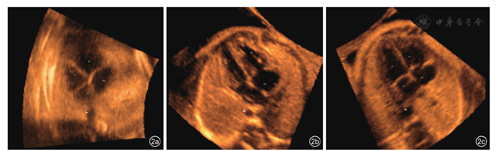

运用5D Heart分析软件,通过顺序标记胎儿心脏的7个解剖结构,自动生成并显示胎儿心脏超声检查的9个标准诊断切面。这些结构分别是:(1)腹部胃泡水平横切面的腹主动脉中心;(2)4CV的胸主动脉中心;(3)4CV的"十字交叉";(4)4CV的右心房壁;(5)3VT的肺动脉瓣;(6)3VT的上腔静脉;(7)主动脉横弓切面的主动脉横弓中心。生成的9个胎儿心脏超声检查标准切面分别是(图1):3VT、4CV、5CV、LVOT、大动脉短轴/RVOT、胃泡水平腹部横切面、动脉导管弓切面、主动脉弓切面及上下腔静脉长轴切面。随后应用内置的VIS-Assistance®对上述所获取的9个标准切面进一步优化后处理并存储图像。

图1 5D Heart显示的正常胎儿心脏超声的9个诊断切面。图a为三血管气管切面;图b为四腔心切面;图c为五腔心切面;图d为左心室流出道切面;图e为右心室流出道切面;图f为胃泡水平腹部横切面;图g为动脉导管弓切面;图h为主动脉弓切面;图i为上下腔静脉右心房切面;每个切面自动标记解剖结构、胎儿左、右及头尾侧